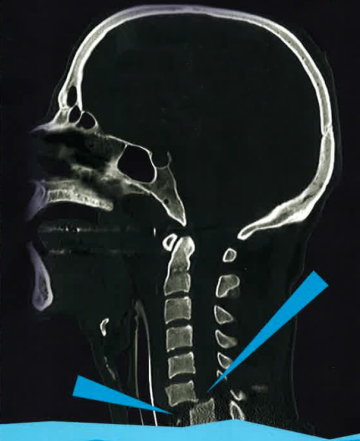

Pro vaši informovanost bych ještě rád zmínil mechanismus vzniku úrazu. Pokud je skákaná tzv. šipka, je prvním tvrdším letícím předmětem o vysoké kinetické energii hlava. Poté následuje krční páteř a dále opět část těla s vyšší tuhostí, tedy hrudní koš, následovaný břichem a dolními končetinami. Veškerá decelerační energie vznikající nárazem hlavy na překážku (dno) se tedy koncentruje na místo nejmenšího odporu, tedy krční páteř (samozřejmě nelze vyloučit, že je při skoku poraněna i hlava nebo hrudní páteř). Dochází k rozlomení obratle (nejčastěji C5, nebo C6 a C7) s tlakem úlomku do páteřního kanálu a poškození míchy.